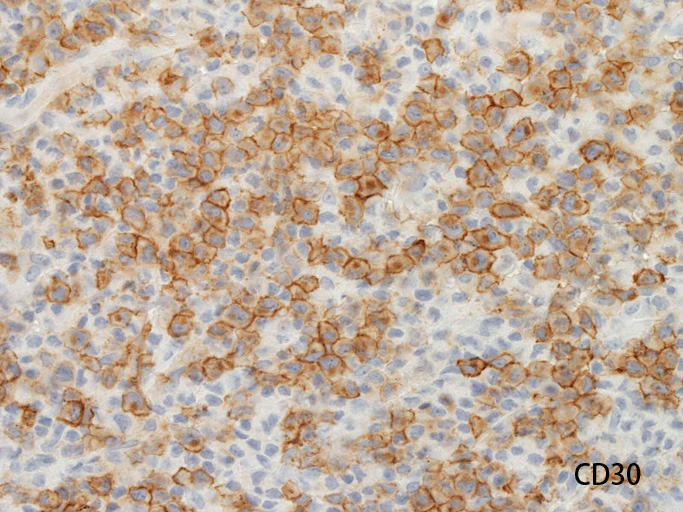

免疫染色所見

ALK/p80が細胞質・核に陽性となる。大型類円形核の細胞以外に, やや小型の類円形細胞に陽性細胞が認められるようです。背景細胞の多くはALK陰性。

ALKは核, 細胞質いずれにもびまん性に染まるパターンです。CD3, CD20は陰性でnull cellの様ですがCD45RO(UCHL-1)が膜に陽性となっています。